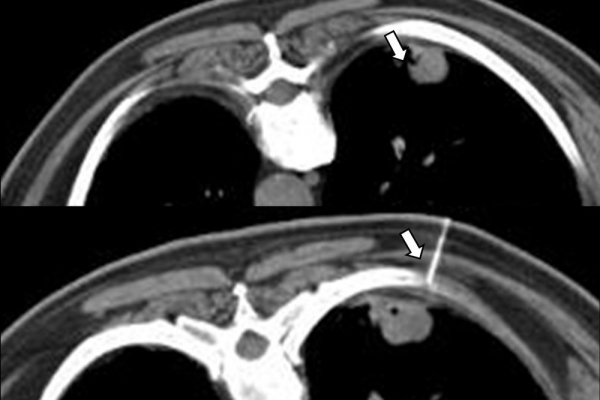

Η διαδερμική βιοψία είναι μία ελάχιστα επεμβατική μέθοδος λήψης υλικού από τον όγκο για κυτταρολογική και ιστολογική εξέταση, από εστιακές αλλοιώσεις του ήπατος, πνεύμονα, νεφρού κλπ. Συστήνεται από τον κλινικό ιατρό ανάλογα με το είδος και το μέγεθος της βλάβης και πραγματοποιείται με ασφάλεια από επεμβατικό ακτινολόγο με την καθοδήγηση αξονικού τομογράφου ή υπερήχων. Στη σύγχρονη ογκολογική θεραπεία όπου γίνεται προσπάθεια καταπολέμησης του καρκίνου σε μοριακό επίπεδο κρίνεται αναγκαία η ακριβής ιστολογική ταυτοποίηση του όγκου ώστε να εφαρμοσθεί εξατομικευμένη θεραπεία για το βέλτιστο αποτέλεσμα. Οι κατευθυνόμενες βιοψίες στοχευουν στο να παρέχουν στον κλινικό ογκολόγο το απαραίτο ιστοπαθολογικό υλικό που θα του επιτρέψει να εφαρμόσει την κατάλληλη θεραπεία για τον ογκολογικό ασθενή.